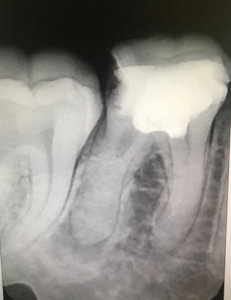

У меня зуб болит. Я его лечила 3 года назад. Мне поставили штифт в декабре 2015, он опять заболел, сделали снимок, оказалось, что он был плохо пролечен. Сняли пломбу, смогли пройти только один канал, во втором канале материал, третий мне врач не смог пройти (инструмент упирался в десну). Тогда еще врач сказал, что этот зуб только удалять, я не согласилась на удаление и мне его просто перекрыли пломбой, теперь опять побаливает.

Как думаете, нужно удалять или его еще можно спасти?

В зубе имеется перфорация, к сожалению, такой зуб спасти и сохранить невозможно.